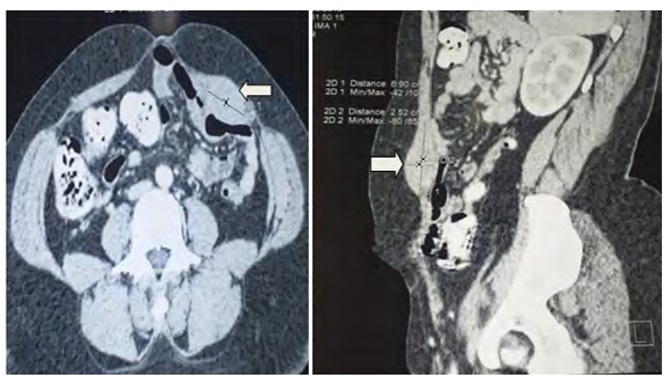

She was a 32-year-old female patient with no particular medical history. She presented intermittent chronic pain in left hypochondrium without digestive or urinary disorders. Physical examination found android obesity with a BMI of 37 kg/m2. Hemodynamic constants were normals and abdominal palpation revealed a homogeneous painless fixed firm parietal mass of approximately 5 cm below the left rib margin. Biologicals examens were normals. The injected abdominal CT revealed a tissue lesion of left rectus muscle of 69 mm x 25 mm x 35 mm well limited, homogeneously enhanced in favor of a benign tumor (desmoid tumor or Rhabdomyoma) (Figure 1). Surgical excision of the mass under general anesthesia was performed (Figures 2 and 3). Following were simples. Histological examination returned in favor of a rhabdomyoma without signs of malignancy. After 19 months of follow-up, no recurrence was reported.

Figure 1: CT images of the tumor (white arrow) developed at the expense of the left rectus abdominis muscle of the abdomen.